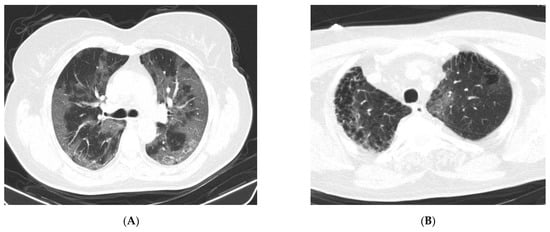

3.4. CT Changes in Patients Suspected of Having COVID-19

| Ground-glass opacities | 9 | 45.0 | 34 | 14.6 | 0.002 | 3.99POS | 1.76–12.4 |